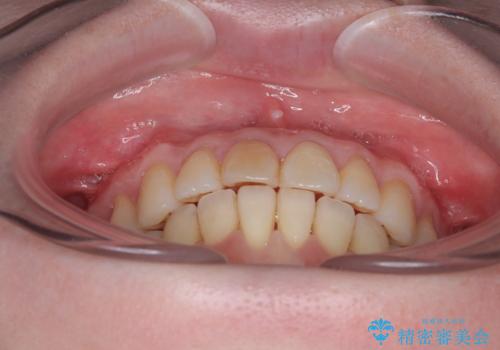

前歯のデコボコをインビザライン・モデレートで矯正治療

- 上下前歯のデコボコを気にして来院された患者様です。

安価なインビザラインパッケージを用いての治療を希望されており、デコボコの程度が中等度であったため、インビザライン・モデレートを用いて矯正治療を行うこととしました。

インビザライン・モデレートは、製作できるアライナーの枚数に制限があるため、移動可能な量に限りがあるものの、インビザライン・ライトよりも枚数が多いため、幅広い症例に対応可能です。